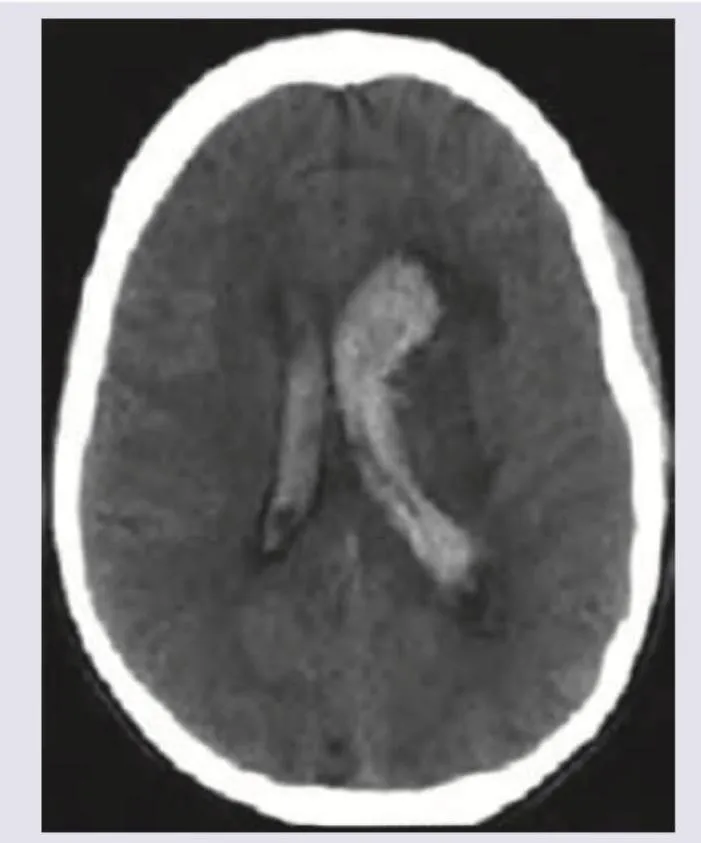

🚩 Red Flags: INR >8, intracranial bleeding, uncontrolled bleeding despite measures, platelets <50×10⁹/L

Visual Aid